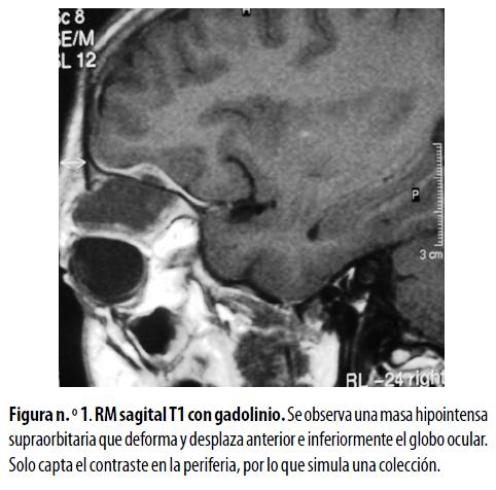

Niña de 6 años, residente en zona rural, llevada a la consulta porque presentaba proptosis progresiva derecha. No refería alteración visual ni otros síntomas de importancia. El desarrollo psicomotor era normal para la edad. Con la sospecha clínica de una masa retrocular, se le hizo una TC de órbitas que mostró una imagen con densidad de tejidos blandos localizada en el techo de la órbita con extensión al espacio retrocular; la lesión afectaba el músculo recto superior pero no invadía el globo ocular, ni el nervio óptico ni las superficies óseas. Ante la necesidad de caracterizar mejor el alcance de la lesión en los tejidos blandos se hizo una RM que reveló una lesión hipointensa con estos en las imágenes sopesadas en T1, con realce anular después de la administración de gadolinio (figura nº. 1) e hipointensidad en las secuencias ponderadas en T2 que evidenció un alto contenido celular. La biopsia demostró un sarcoma granulocítico. Como no existían antecedentes ni sospecha de leucemia, se le hicieron estudios complementarios de médula ósea y sangre periférica que evidenciaron una LMA como enfermedad de base.